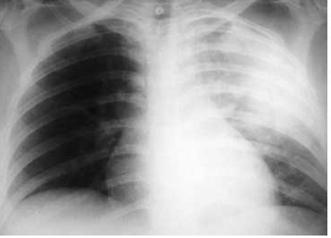

Edema agudo de pulmón

Se produce cuando el infarto afecta a más del 25 % del ventrículo izquierdo y la presión capilar pulmonar es > 25 mmHg.

Se indica furosemida en bolo EV ( precarga).

Shock cardiogénico

Aparece cuando el infarto afecta a más del 40 % del ventrículo izquierdo. Hay hipotensión (presión sistólica menor de 90 mmHg) y datos de hipoperfusión, como oliguria, acidosis metabólica o índice cardíaco bajo (< 2.2 L/minuto/m 2).

Se recomienda inotrópicos (norepinferina o dobutamina).

Tenemos el score de Killip que establece una clasificación clínica radiológica al ingreso del paciente con SCACEST.

También contamos con el score de Forrester, que correlaciona datos hemodinámicos, como índice cardíaco (IC) y presión capilar pulmonar (PCP), así como datos clínicos en los pacientes que sufren una insuficiencia cardiaca tras un infarto de miocardio (IC normal es > 2.2 L/minuto/m 2 y PCP normal < 18 mmHg).

Clase Hallazgos clínicos Mortalidad I Sin signos ni síntomas de 0 a 5%

estertores o crepitantes, 3er ruido o aumento de PV

10 a 20%

Edema pulmonar 35 a 45%

Shock cardiogénico: hipotensión y vasoconstricción periférica

85 a 95%